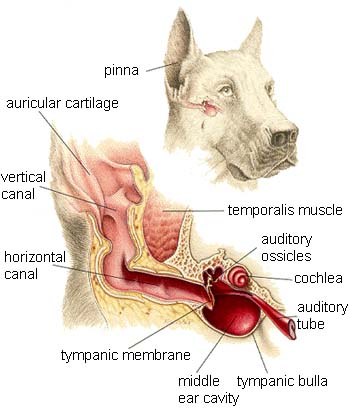

The organs of special senses allow the animal to interact with its environment; sight, taste, smell and hearing.

Dog Ears